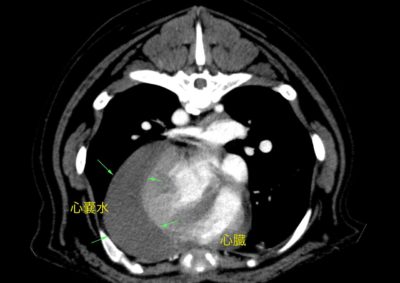

心タンポナーデ+腹腔内出血によるショック